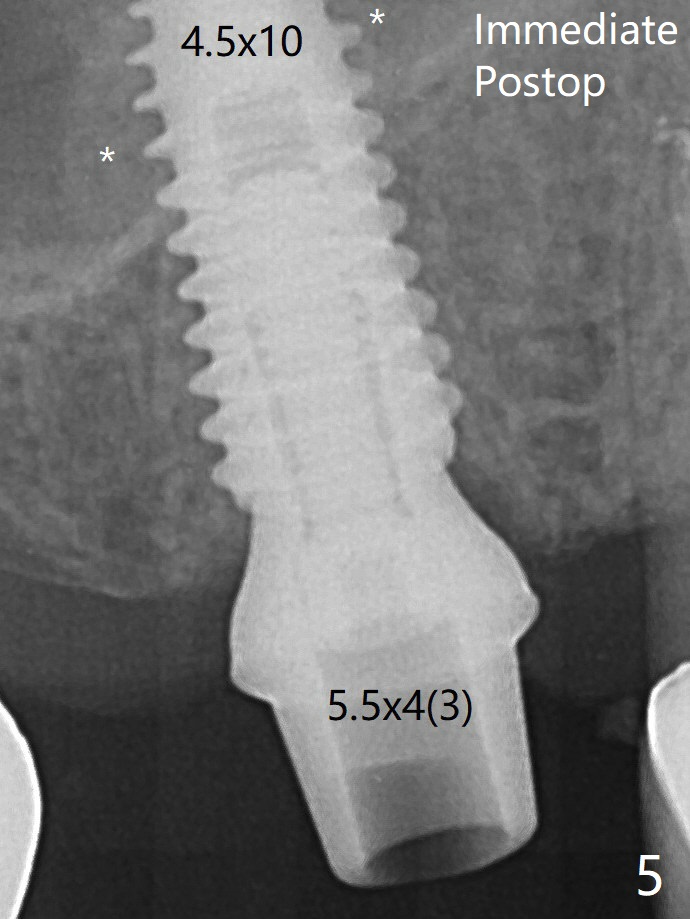

There is no obvious bone loss 7 months postop (Fig.7).